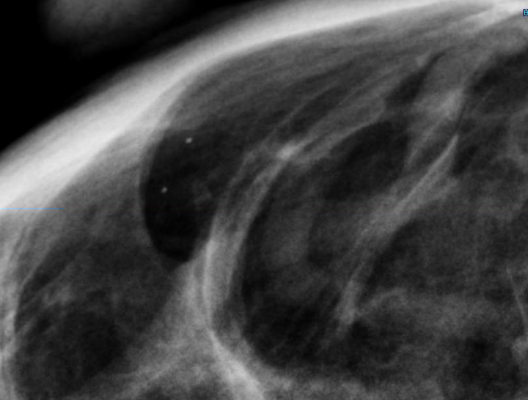

Response to Neoadjuvant Chemotherapy and Tumor Subtype Are Strong Predictors of Loco-regional Breast Cancer Recurrence: A large study provided new insight on the factors affecting loco-regional breast cancer recurrence in women treated with chemotherapy before surgery. The findings could help to better identify women who may benefit from receiving radiotherapy after surgery to reduce the risk of recurrence.